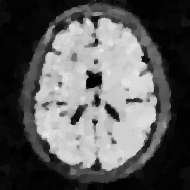

We now want to discuss the experimental setup. We want to reconstruct the synthetic brain phantom in Figure 1(a) from sub-sampled k-space measurements. The numerical phantom is based on the design in [1] with a matrix size of . It consists of several different tissue types like cerebrospinal fluid (CSF), gray matter (GM), white matter (WM) and cortical bone. Each pixel is assigned a set of MR tissue properties: Relaxation times and and spin density . These parameters were also selected according to [1]. The MR signal in each pixel was then calculated by using the signal equation of a fluid attenuation inversion recovery (FLAIR) sequence [5]:

The sequence parameters were selected: TR = 10000 ms, TE = 90 ms. TI was set to 1781 ms to achieve signal nulling of CSF ( with ).

In order to generate artificial k-space measurements for each coil, we proceed as follows. First, we produce 8 images of the brain phantom multiplied by the measured coil sensitivity maps shown in Figure 1(c) - 1(j). The coil sensitivity maps were generated from the measurements of a water bottle with an 8-channel head coil array. Then we produce artificial k-space data by applying the 2D discrete Fourier-transform to each of those individual images. Subsequently, we sub-sample only approx. 25% of each of the k-space datasets via the spiral shown in Figure 1(b). Finally, we add Gaußian noise with standard deviation to the sub-sampled data.

6.2.1 Low noise level

We have computed reconstructions from the noisy data with noise level via Algorithm 1, with regularisation parameters set to , and for . We have further created a naïve reconstruction by averaging the individual inverse Fourier-transformed images obtained from zero-filling the k-space data. The modulus images of the results are visualised in Figure 2. The results are visualised in Figure 3. The PSNR values for the averaged zero-filled reconstruction is 10.2185, whereas the PSNR of the reconstruction with the proposed method is 24.5572.